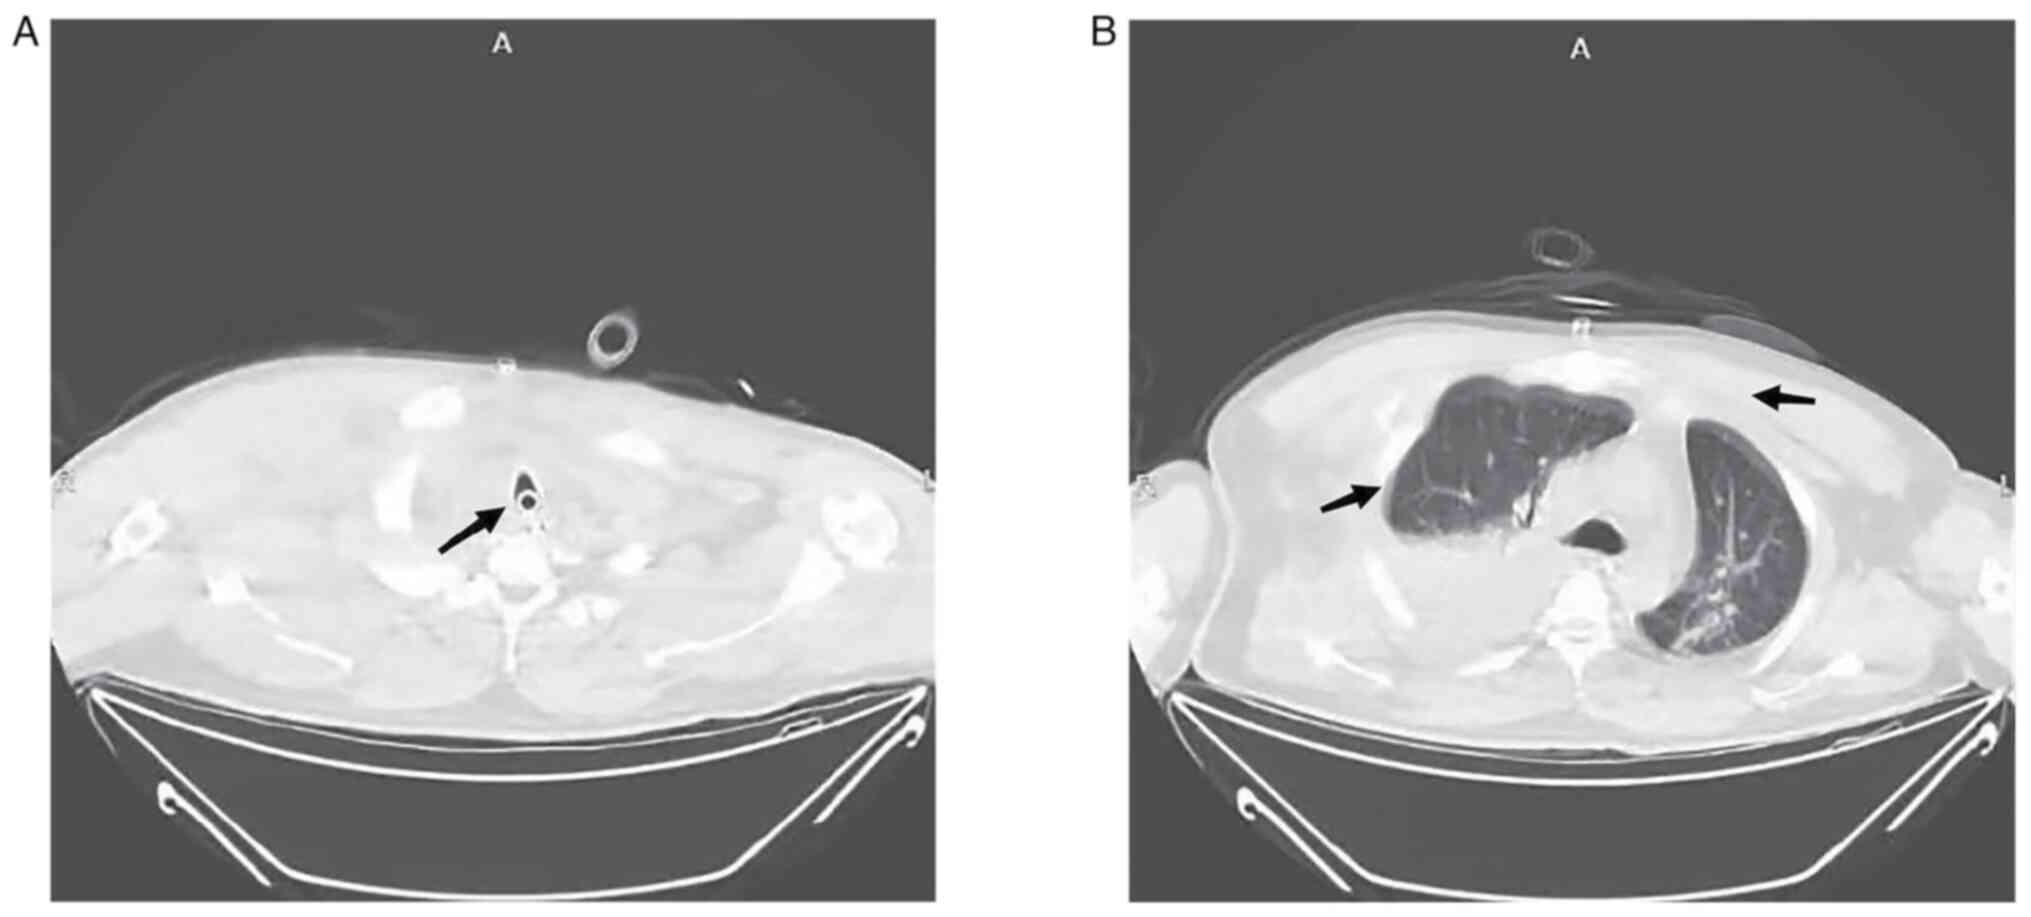

Figure 2

CT scan of the patient's chest on admission (axial view). (A) The black arrow indicates collapse of the main bronchus. (B) The black arrow indicates pneumothorax, lung compression and massive subcutaneous emphysema of the chest wall.

A 39-year-old man was crushed by an excavator during the course of his work in July 2022. The patient experienced severe chest pain immediately after the injury, as well as chest tightness and shortness of breath, dyspnea and continuous hemoptysis, without hematemesis. The patient presented to the emergency room of Jiashan First People's Hospital (Jiaxing, China) 30 min after the injury occurred, where they were admitted with clear consciousness and dysphoria, a body temperature of 36.2˚C, heart rate of 112 beats/min (bpm), respiration rate of 38 breaths/min, blood pressure of 107/72 mmHg and oxygen saturation (SPO2) of 92%. Upon examination of the patient, there was swelling and bruising in the neck, massive subcutaneous emphysema on both sides of the chest wall and beneath the abdominal wall, drum sounds on percussion of both lungs and a loss of breath sounds on auscultation. On physical examination, the patient's oxygen saturation had declined to <80%, tracheal intubation was performed immediately and CT was performed. CT examination demonstrated multiple air accumulations in the cerebral sulcus, cerebral fissure and ventricles, collapse of the main bronchus, bronchial occlusion on both sides, pneumothorax on both sides with partial lung tissue inflation, 70% lung compression, multiple rib fractures on both sides, massive subcutaneous emphysema on both sides of the chest wall, fracture of the right scapula and fracture of the right clavicle (Figs. 1 and 2). The results of the blood gas analysis were as follows: Partial pressure of oxygen (PaO2), 51.3 mmHg (normal range: 80-100 mmHg); partial pressure of carbon dioxide, 67.2 mmHg (normal range: 35-45 mmHg); base excess, -8.4 mmol/l (normal range: -3-+3 mmol/l); pH, 7.15 (normal range: 7.35-7.45); lactate level, 4.5 mmol/l (normal range: 0.5-2.2 mmol/l); and hemoglobin level, 104 g/l (normal range: 130-175 g/l).